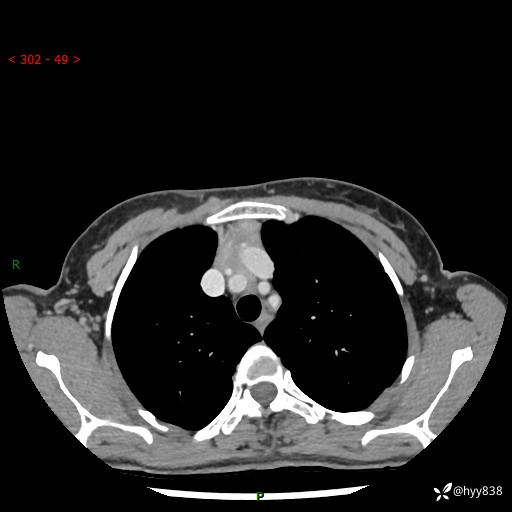

胸部CT平扫